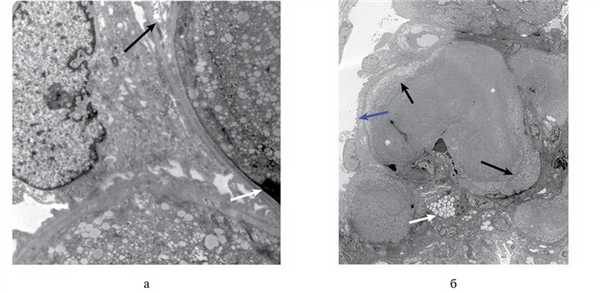

При ультраструктурном исследовании наблюдались признаки слияния цитоподий, цитоплазматические вакуоли подоцитов и очаговое расщепление базальных мембран (рис. 3, а). В просвете капиллярных петель располагались липопротеиновые тромбы, состоявшие из концентрических слоев вакуолей различного размера, напоминавшие местами «отпечатки пальцев». Просвет капилляров заполнен этими массами с секвестрированием в них эритроцитов. Аналогичный вакуолизированный материал местами отмечался в мезангиальном матриксе (рис. 3, б).

Рис. 3. Трансмиссионная электронограмма. а — вакуоли в просвете капилляра формируют ламинарные слои «липопротеинового тромба». Участок расщепления базальных мембран (черная стрелка). Субэндотелиальный депозит (белая стрелка), ×9500; б — интракапиллярные тромбы, состоящие из концентрических слоев (черные стрелки) мелковакуолизированного материала — «липопротеиновые тромбы». Локально вакуолизированный материал располагается в мезангии (белая стрелка) и в участках расщепления базальных мембран (синяя стрелка), ×3000.

Ультраструктурный анализ обычно позволяет уточнить специфические структурные изменения в клубочках при ЛПГ. В частности, в просвете исследованных капилляров у нашего больного наблюдались тромбоподобные субстанции, состоящие из характерных для данной патологии вакуолей различного размера, формировавших концентрические слои, иногда напоминающие «отпечатки пальцев» (см. рис. 3, б). В периферических базальных мембранах отмечалось их сегментарное расщепление (см. рис. 3, а). Липидный материал накапливался не только в просвете капилляров, но также субэндотелиально и в мезангиальном матриксе (см. рис. 3, б). Для подоцитов характерно слияние отростков и накопление в цитоплазме умеренного количества липидных вакуолей. Кроме того, очаговые электронно-плотные отложения наблюдались в мезангии и субэндотелиально.